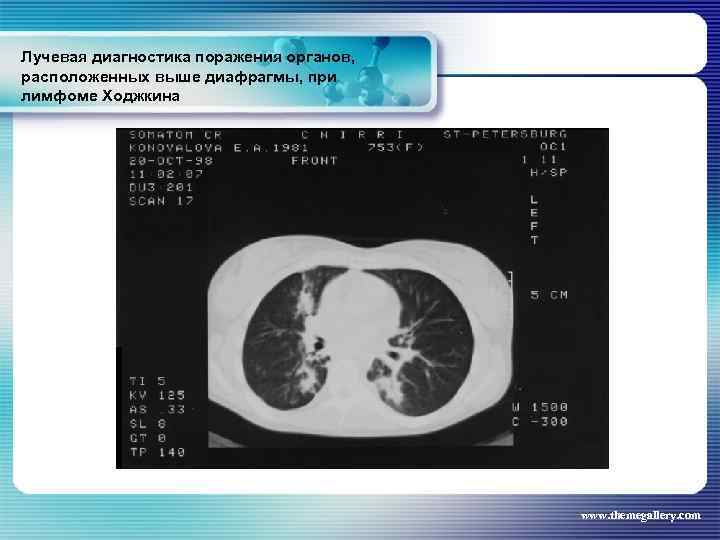

Лучевая диагностика поражения органов, расположенных выше диафрагмы, при лимфоме Ходжкина Частота поражения органов грудной полости при лимфоме Ходжкина: поражение средостения легких плевры грудной стенки - 66, 7 % 33, 75% 5, 3% 1, 8% www. themegallery. com

Лучевая диагностика поражения органов, расположенных выше диафрагмы, при лимфоме Ходжкина Частота поражения органов грудной полости при лимфоме Ходжкина: поражение средостения легких плевры грудной стенки - 66, 7 % 33, 75% 5, 3% 1, 8% www. themegallery. com